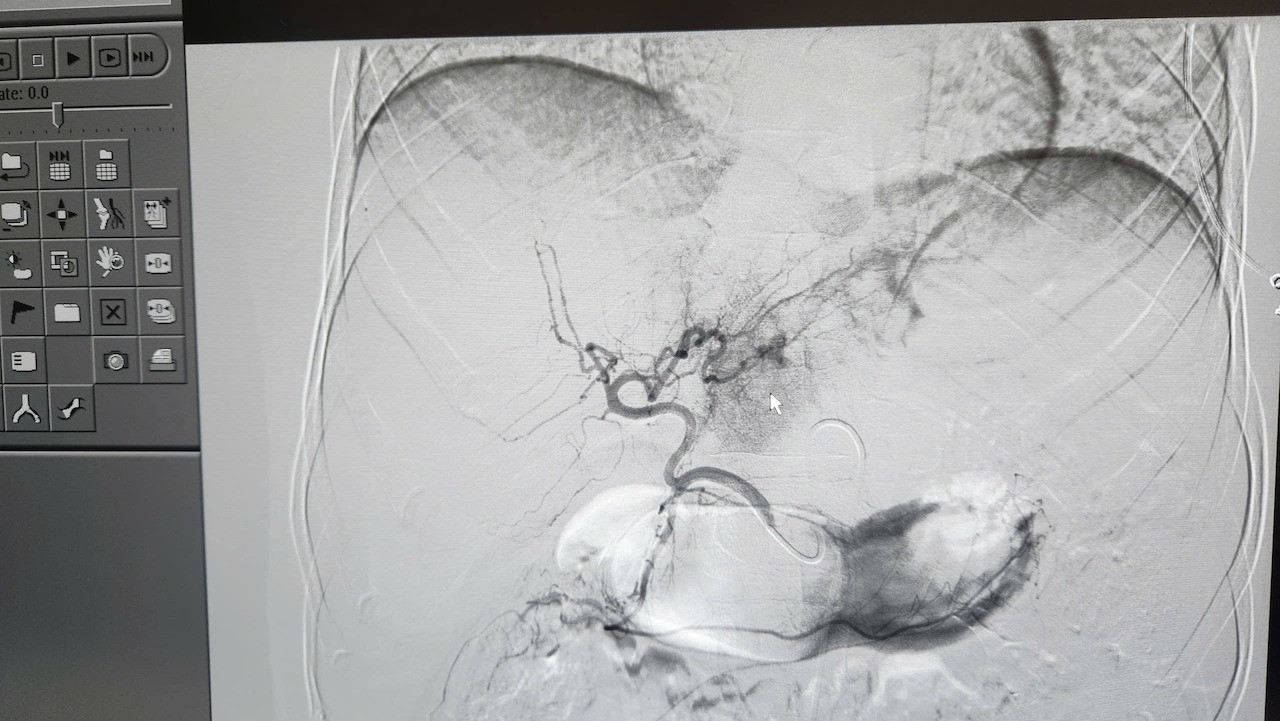

Kết quả chụp CT cho thấy bệnh nhân bị vỡ gan độ IV, ổ chảy máu đang hoạt động mạnh. Đây là tình trạng nguy kịch, nguy cơ tử vong rất cao nếu không được xử trí kịp thời.

Hình ảnh lá gan bị vỡ của bệnh nhân. Ảnh: BVCC

Ca can thiệp do ê-kíp can thiệp mạch của Khoa Chẩn đoán hình ảnh thực hiện với sự chỉ đạo trực tiếp của bác sĩ CKII Ngô Vĩnh Hoài, Phó Trưởng khoa. Nhờ hệ thống chụp mạch số hóa xóa nền (DSA), các bác sĩ đã xác định chính xác vị trí tổn thương và kiểm soát hoàn toàn điểm chảy máu.